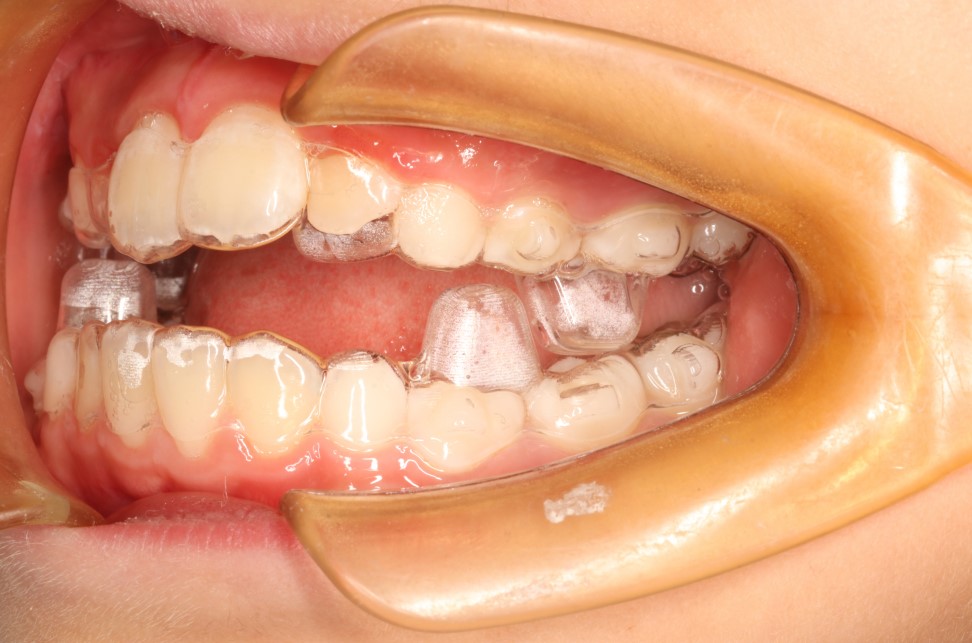

2018年《第四次全国口腔健康流行病学调查报告》显示,我国儿童错颌畸形总体患病率已高达74%,相当于约1.05亿儿童存在牙齿排列或颌骨发育异常。

这意味着,平均每4名儿童中就有3名面临牙齿前突、拥挤、咬合不正等问题。然而,与此形成鲜明对比的是,我国错颌畸形儿童的实际就诊率仅为4%左右。